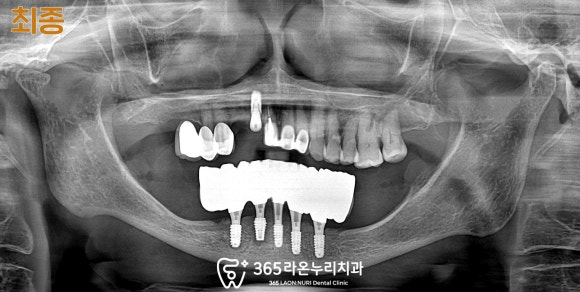

■ 5. 최종 보철 수복

하악 진료가 모두 마무리된 모습입니다.

픽스처의 고정력도 충분하고

적응도 잘 하셨기에 빠르게 마무리해 드릴 수 있었네요.

물론 위 앞니 브릿지 부근이 안 좋으셔서

현재도 치료 중이긴 하나

하악과 마찬가지로 플리퍼라는 장치를 이용하여

주변 사람들이 알아차리지 못하게

잘 진료해 드리고 있습니다.^^

상악의 치료가 끝나고 나면

그 과정도 한 번 더 다뤄드리겠습니다.